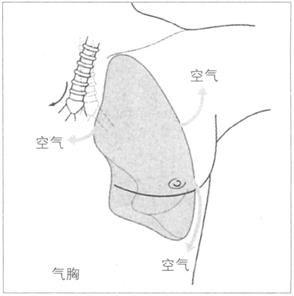

叩诊通常从双侧肺尖叩起,可以直接叩双侧锁骨,接着对双侧上、中、下三个区域进行对比,需要强调的是必须叩双侧腋下,因为右肺中叶及舌叶的病变多出现在该区域。叩诊要点在于鉴别清音的改变。正常时,肺部充满气体(中空),叩诊应为清音。如果肺组织塌陷或实变,叩诊呈实音(因为固体对声音的传导不如气体,图72),如果胸腔内积液,则叩诊浊音(原因是液体对震动的传导弱于气体,图73),若胸腔内积气,如气胸,叩诊音为过清音(图74)。各种影响叩诊音的因素参见表20。

①周围性发绀及周围静脉扩张是由COPD引起的CO2潴留的主要特征(图76)。②脊柱侧后凸常预示患者有某种呼吸系统疾病的倾向(图77)。③结核的X线表现(图78)。④肺尖部结核所致的纤维化多引起上胸部变平(图79),由于脊柱常受累,故多有成角。⑤支气管肺癌(图80)。⑥大叶肺炎患者常伴发单纯疱疹病毒感染(图81、图82)。⑦如肺组织萎陷(如气胸),则胸片上无法看到肺纹理(图83)。